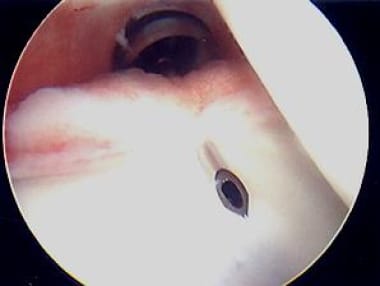

The images below show posterior plication and are representative. The view is of a left shoulder from the anterosuperior portal, just anterior to the biceps long head, aimed in a posteroinferior direction. The patient is in the lateral decubitus position, with the arm in 5 lb of traction, positioned in 45° of abduction and 20° of forward flexion. The working portal is the typical posterior portal, which is 1.5 cm inferior and 1.5 cm medial to the posterior corner of the acromion.

First, a suture passer device (Spectrum; ConMed Linvatec, Largo, FL) is placed through the working cannula; next, it is initially passed through a pinch of posterior capsule 1 cm from the labrum and then through the posterior labrum itself (see the image below).

Suture passer device (Spectrum; ConMed Linvatec, Largo, FL) is placed through working cannula, then through "pinch" of posterior capsule, and also through posterior labrum. Photo courtesy of Daniel C Wnorowski, MD.